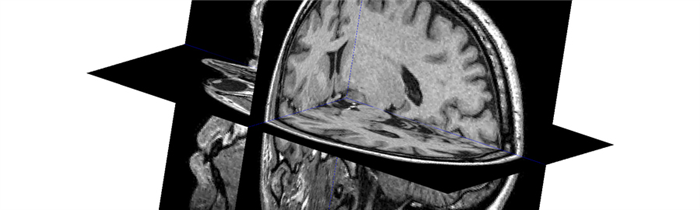

Системы нейронавигации для планирования доступа и визуального контроля функционально важных трактов и корковых зон вокруг опухоли;

Радиохиругическое лечение глиомы на Киберноже, независимо от типа опухоли, который более точно можно будет определить во время биопсии (если есть возможность ее провести), проводится по одинаковому алгоритму. Сначала с помощью данных КТ- и МРТ-исследований будет сформирована пространственная модель расположения опухоли и соседствующих с ней здоровый участков мозга. Затем в планировочной системе лучевой терапевт задает требуемую дозу, которую КиберНож должен сформировать в области, в границах которой находится глиома.

Также задается минимальная доза в тех зонах, которым любое облучение противопоказано (например, ствол головного мозга). После этого мощная компьютерная система строит план лечения с тем, чтобы из множества тонких одиночных пучков излучения сформировать в опухолевой зоне равномерную зону требуемой дозы излучения. Далее роботизированная рука-манипулятор КиберНожа согласно составленному плану будет последовательно перемещать компактный линейный ускоритель в каждое из запланированных положений, из которых будет проводится подача единичного пучка.